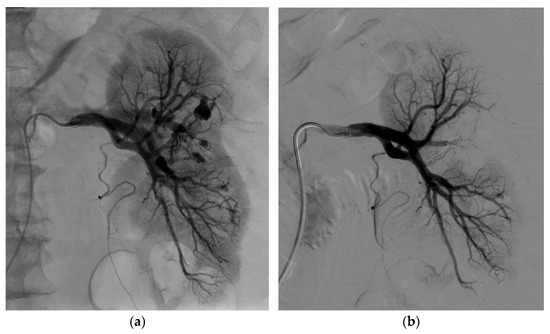

3.2. Endovascular Treatment

| Iatrogenic vascular lesion | |

| Number of renal false arterial aneurysms | 47 |

| Number of renal arteriovenous fistulas | 9 |

| Number of patients with both | 7 (28%) |

| Aneurysm size (mm) | 10.5 (±4.7) |

| Embolization technique | |

| Coils | 8 (32%) |

| Liquid embolic agent | 8 (6 Glubran2, 1 Onyx, 1 Gelatispon) (32%) |

| Coils and liquid embolic agent | 9 (36%) |

| Technical success at first attempt | 24 (96%) |

| Technical success at first or second attempt | 25 (100%) |

| Clinical success, one attempt | 24 (96%) |

| Clinical success, one or two attempts | 25 (100%) |